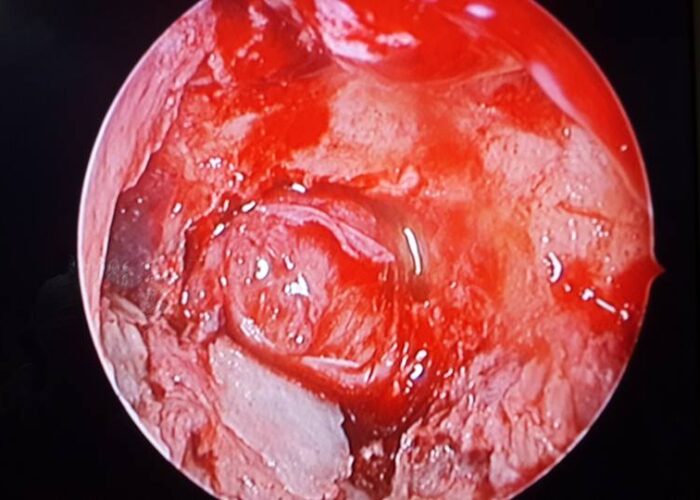

3 Endoscopic Pituitary Cases in Manik Hospital